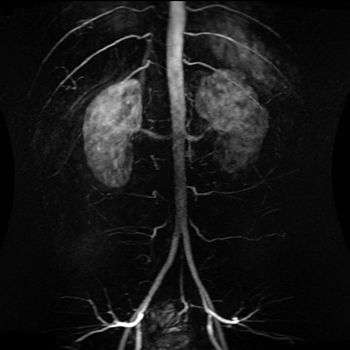

Abdominal aorta

The abdominal aorta is the largest artery in the abdominal cavity. As part of the aorta, it is a direct continuation of the descending aorta (of the thorax).

The abdominal aorta begins at the level of the diaphragm, crossing it via the aortic hiatus, technically behind the diaphragm, at the vertebral level of T12. It travels down the posterior wall of the abdomen, anterior to the vertebral column. It thus follows the curvature of the lumbar vertebrae, that is, convex anteriorly. The peak of this convexity is at the level of the third lumbar vertebra (L3). It runs parallel to the inferior vena cava, which is located just to the right of the abdominal aorta, and becomes smaller in diameter as it gives off branches. This is thought to be due to the large size of its principal branches. At the 11th rib, the diameter is 122mm long and 55mm wide and this is because of the constant pressure.

The abdominal aorta supplies blood to much of the abdominal cavity. It begins at T12, and usually has the following branches: